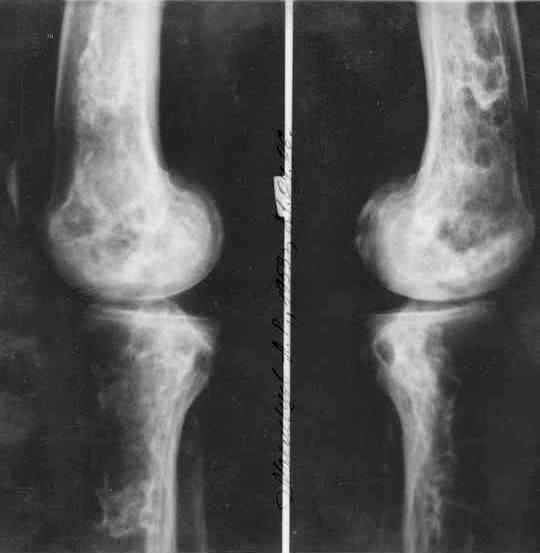

Изменения структуры костей у Вашего пациента больше похожи на полиоссальную форму фиброзной дисплазии или болезнь Педжета, возможены также инфаркты костного мозга б.берцовых костей. К сожалению, качество снимка не очень хорошее, непонятно, сохранен ли кортикальный слой б.берцовых костей по передней поверхности.

Для примера привожу случай из архива американской ассоциации рентгенологов (ACR) - развитие злокачественной фиброзной гистиоцитомы на левой б.берцовой кости у пациента с множественными инфарктами костного мозга (рис 4,5 - левая, рис 6 - правая)